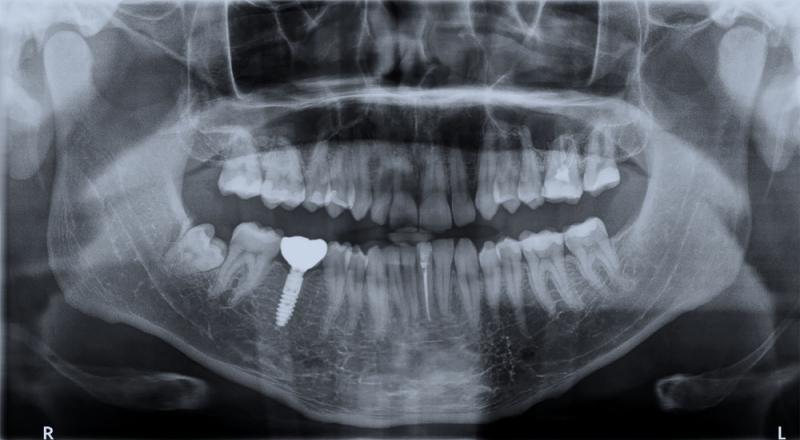

O operacji implantów decyduje chirurg stomatolog. Najpierw zaczynają się konsultacje i planowanie zabiegu, który odbędzie się na podstawie dokładnego zbadania jamy ustnej. Lekarz zleca lub wykonuje badania obrazowe, tj. zdjęcia rentgenowskie, filmy panoramiczne i/lub tomografię komputerową.

Pomagają one dokładnie ocenić jakość i ilość kości szczęki oraz określić, czy w danym miejscu potrzeba na przykład więcej kości. Po ustaleniu szczegółów, pacjent ustala z lekarzem termin zabiegu, podczas którego wszczepia się odpowiednie implanty. Nie trzeba bać się bólu, ponieważ podczas wszystkich wizyt chirurgicznych pacjent zwykle otrzymuje znieczulenie miejscowe, a nierzadko także wszelkie inne środki uspokajające niezbędne dla osiągnięcia komfortu psychicznego.